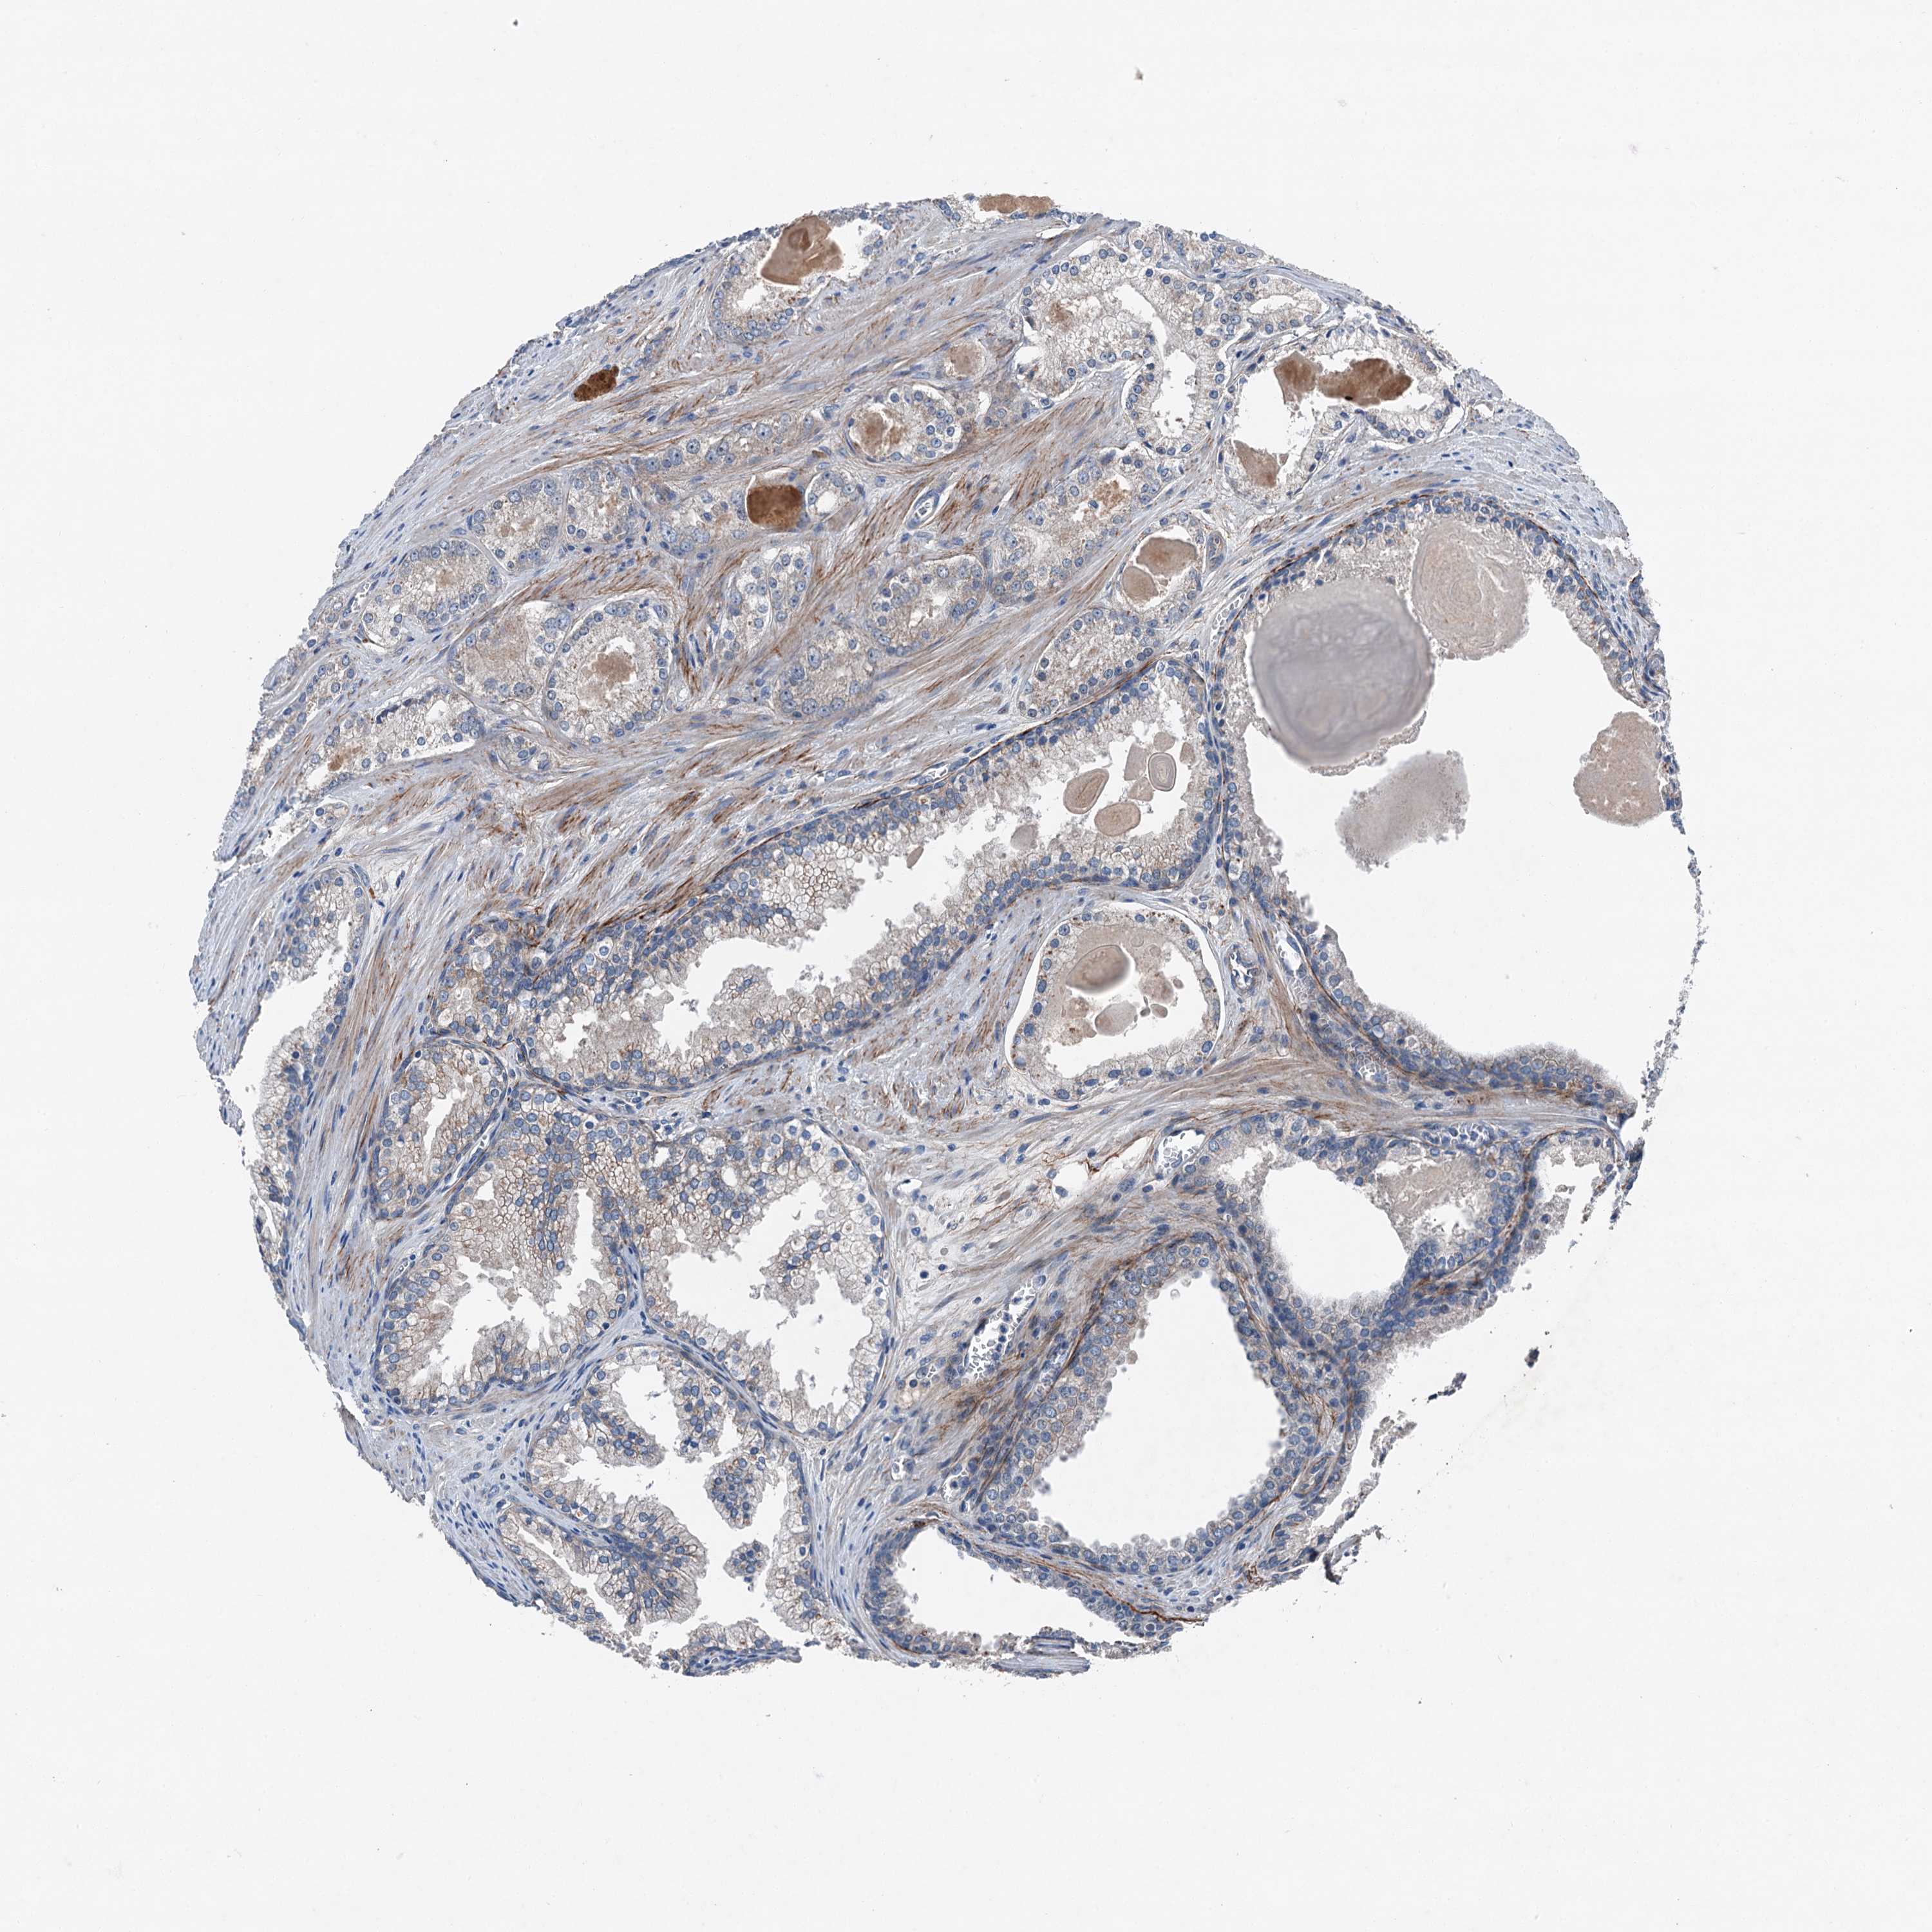

PROSTATE CANCER - Protein expressioni

A mouse-over function shows sample information and annotation data. Click on an image to view it in a full screen mode. Samples can be filtered based on level of antibody staining by selecting one or several of the following categories: high, medium, low and not detected. The assay and annotation is described here.

Note that samples used for immunohistochemistry by the Human Protein Atlas do not correspond to samples in the TCGA dataset.

Antibody stainingi

Antibody staining in the annotated cell types in the current human tissue is reported as not detected, low, medium, or high, based on conventional immunohistochemistry profiling in selected tissues. This score is based on the combination of the staining intensity and fraction of stained cells.

Each image is clickable and will lead to virtual microscopy that enables deeper exploration of all samples and also displays staining intensity scores, fraction scores and subcellular localization as well as patient and tissue information for each sample.

Antibody HPA041015

Staining

High

Medium

Low

Not detected

Intensity

Strong

Moderate

Weak

Negative

Quantity

>75%

75%-25%

<25%

None

Location

Nuclear

Cytoplasmic/membranous

Cytoplasmic/membranous,nuclear

Adenocarcinoma, High grade

Adenocarcinoma, Low grade